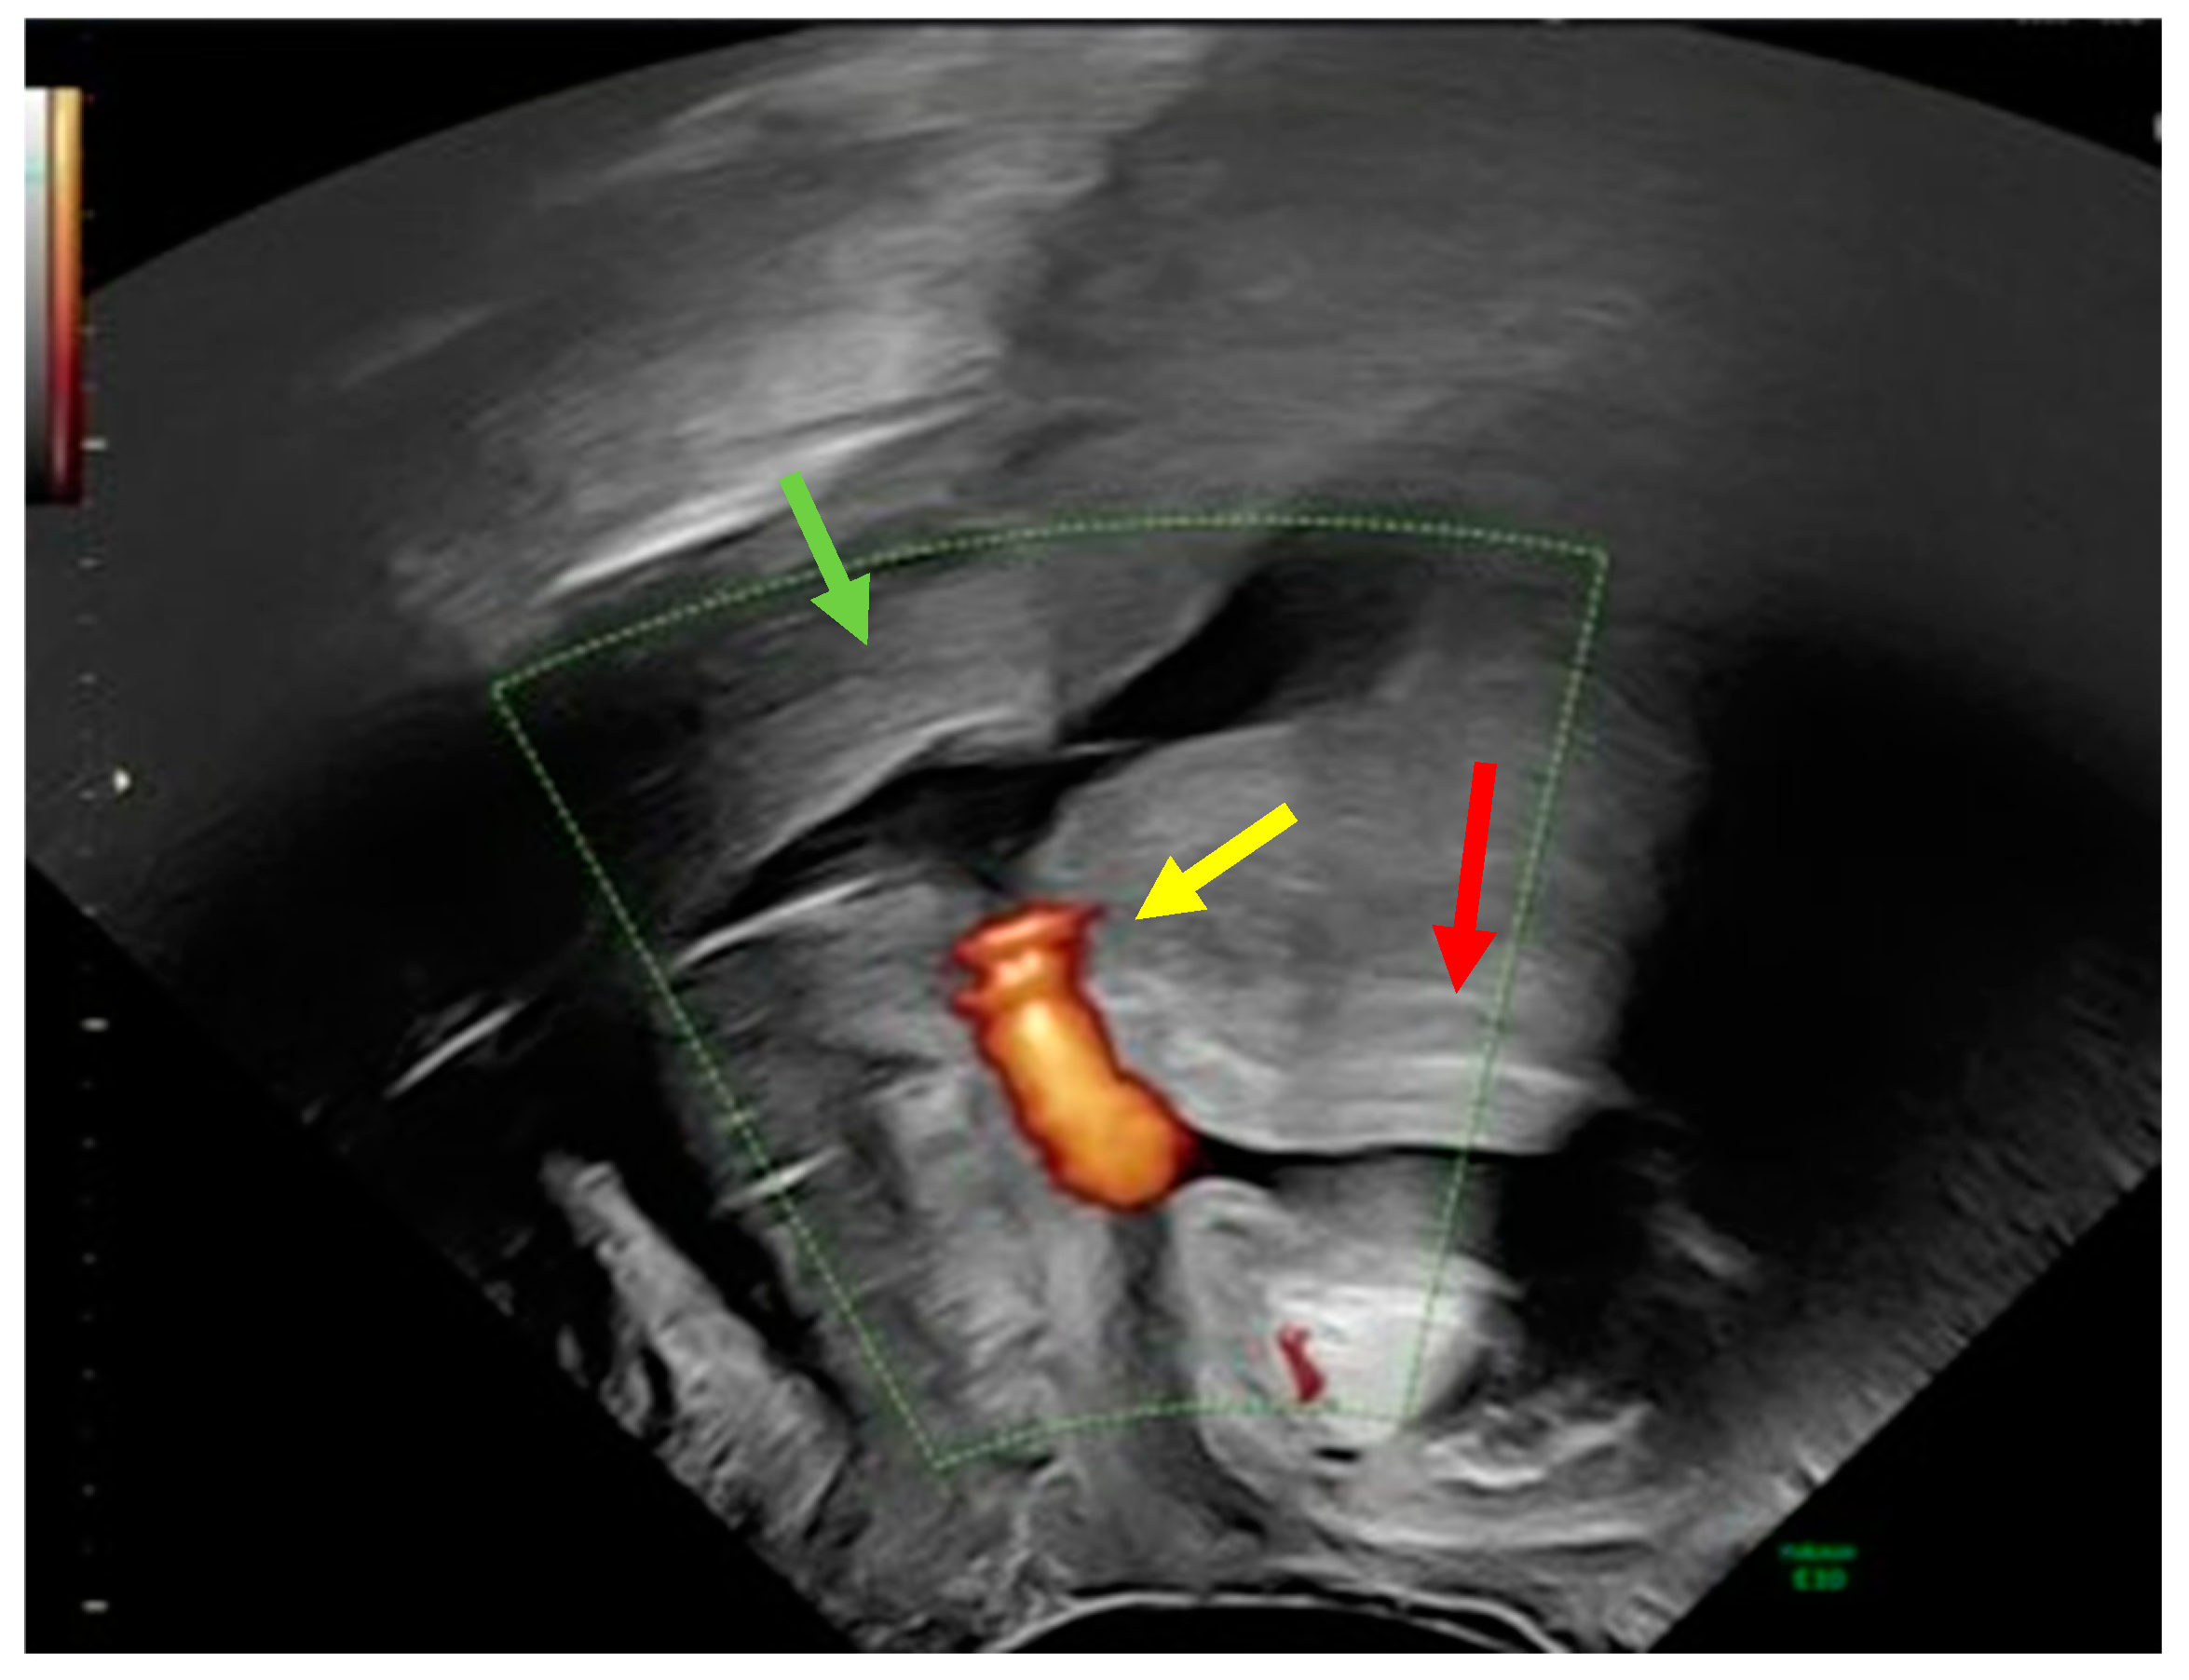

A 32-year-old postnatal mother was referred to our tertiary university center complaining of urine leakage via the cervix uteri after vacuum-assisted delivery with impending fetal asphyxia five days prior to referral. In the past, the patient had delivered a child by cesarean section and another child by vacuum-assisted delivery. Laboratory tests did not reveal any signs of anemia or infection. First, methylene blue was injected into the bladder through a urinary catheter. Blue urine was observed when the speculum was inserted into the vagina, indicating the presence of vesicouterine fistula. In addition, abnormal communication was suspected, as transvaginal ultrasound showed a bladder wall in close contact with the anterior surface of the uterus with no demarcation line (Figure 1).

Figure 1.

Transvaginal ultrasound using power Doppler demonstrating communication (yellow arrow) between the uterine cervix (green arrow) and bladder (red arrow).